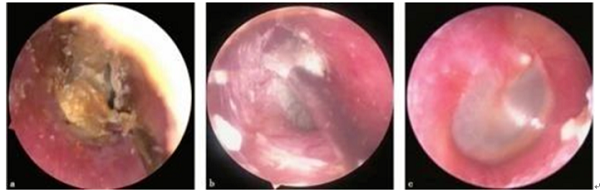

.具体操作流程(耳内镜下):

首先在耳内镜下清理干净外耳道,用抗生素激素类药液冲洗。

a.用钩针、吸管等显微器械将真菌与外耳道皮肤之间分离;b.采用吸管仔细从外耳道及鼓膜表面分离真菌;c.使用细长棉签外耳道表面均匀涂派瑞松乳膏; 由于耳颞区的解剖特点及血迷路屏障的存在,局部途径用药可使药物直接作用于病变部位,充分发挥最大药效。因此耳部疾病的治疗,耳局部用药已成为常用和有效的治疗手段。传统的耳部局部用药方式主要以滴药、浸泡为主,药物可以直接作用于暴露的外、中耳,但对于某些局限性病灶反而不能针对性地精确用药。耳内镜下的耳部给药则更为细致,例如在内镜监视下使用耳科电凝对局灶性病变进行烧灼,可以避免损伤周围正常组织。对于传统的耳部滴药,在患者伴外耳道耵聍、痂皮及分泌物等堵塞时必然会影响药物到达作用部位。在用药前应用耳内镜充分清理后可以准确地投药至所需部位,在局部形成数十甚至数百倍于全身应用时的药物浓度,迅速达到峰值药物浓度,并长时间维持; 虽然局部形成极高的药物浓度,但用药总量及进入血液循环的药量明显少于全身用药,因而大大减少对全身重要脏器产生的毒性不良反应。